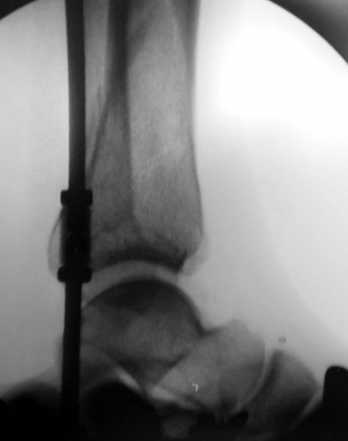

На мой взгляд оптимальным для такого перелома является аппарат Илизарова, который позволяет:

Пример - довольно похожий перелом, оперированный в первые 8 часов после аварии у 40-летнего больного, страдающего тяжёлым сахарным диабетом 1 типа.